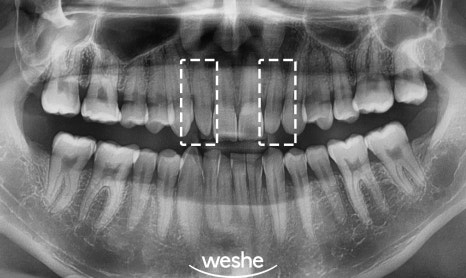

1.왜소치(peg lateralis)란?

정상치아 보다 작고 뾰족한 모양으로

'peg lateralis'라고도 부르는데요.

주로 위턱 측절치,

위턱의 앞니 중 두번째에 위치한 부위에

흔하게 나타나며

12, 22번 부위의 peg lateralis 상황에서

이것을 적용하는 경우가 있는데요.

마곡역 치과 에서는

앞니 왜소치는 단순히 크기만 작은 것이 아니라

형태적인 문제도 같이 동반하는 경우가 많다

판단하고 있습니다.